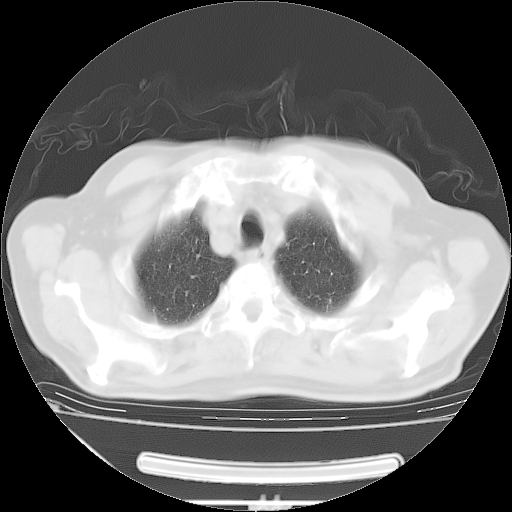

今天复查肺部CT,发现双肺广泛磨玻璃样改变。所以我把3月19日和5月9日相隔50天的肺部CT上传。请大家会诊。

2009年3月19日肺部CT片。

2009年3月19日肺部CT